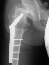

- Age 6: Valgus osteotomy for subluxation and 2cm leg length inequality.

- Age 15: Valgus osteotomy for hip incongruity.

- Age 20: Hip arthroscopy. Hip fusion recommended.

This case is an example of untreated septic arthritis which caused avascular

necrosis of the proximal femur. The primary cause of this is undrained

septic hip. Repeated aspiration is not adequect treatment of a septic hip.